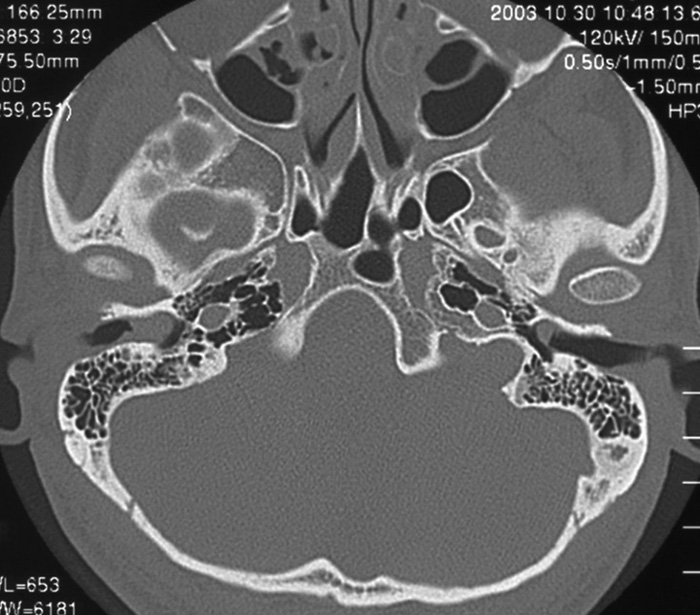

症例5:41歳男性

数日前より右耳痛出現。徐々に聞こえづらくなってきた。

慢性アレルギ―性鼻副鼻腔炎

両側耳垢あり。

特に異常所見なし(炎症所見なし)。

図1